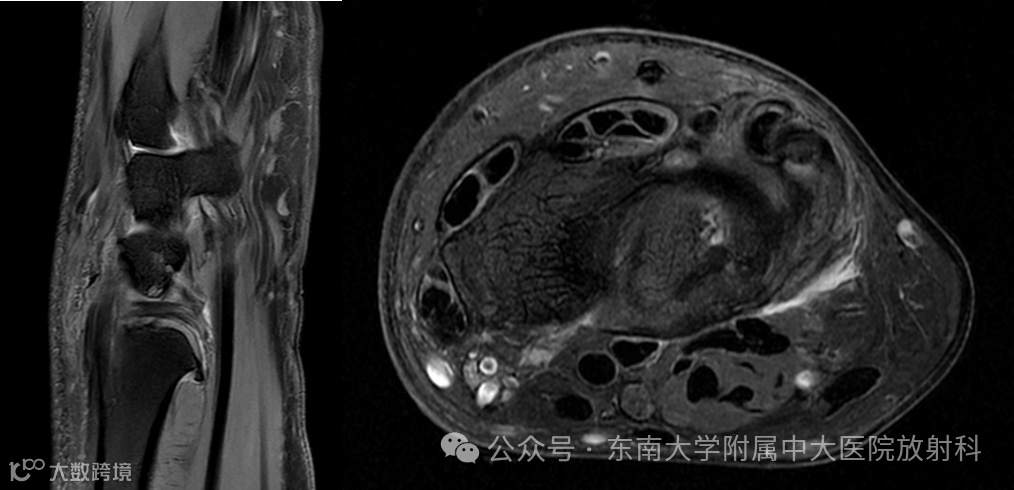

女 ,63岁

主诉:右腕关节疼痛1年

病史:患者1年余前出现右腕关节疼痛,予保守治疗,至今症状未缓解

专科检查:右腕关节稍肿胀、压痛

影像号:3396554,2025-04-01,右腕关节MRI平扫

影像学表现